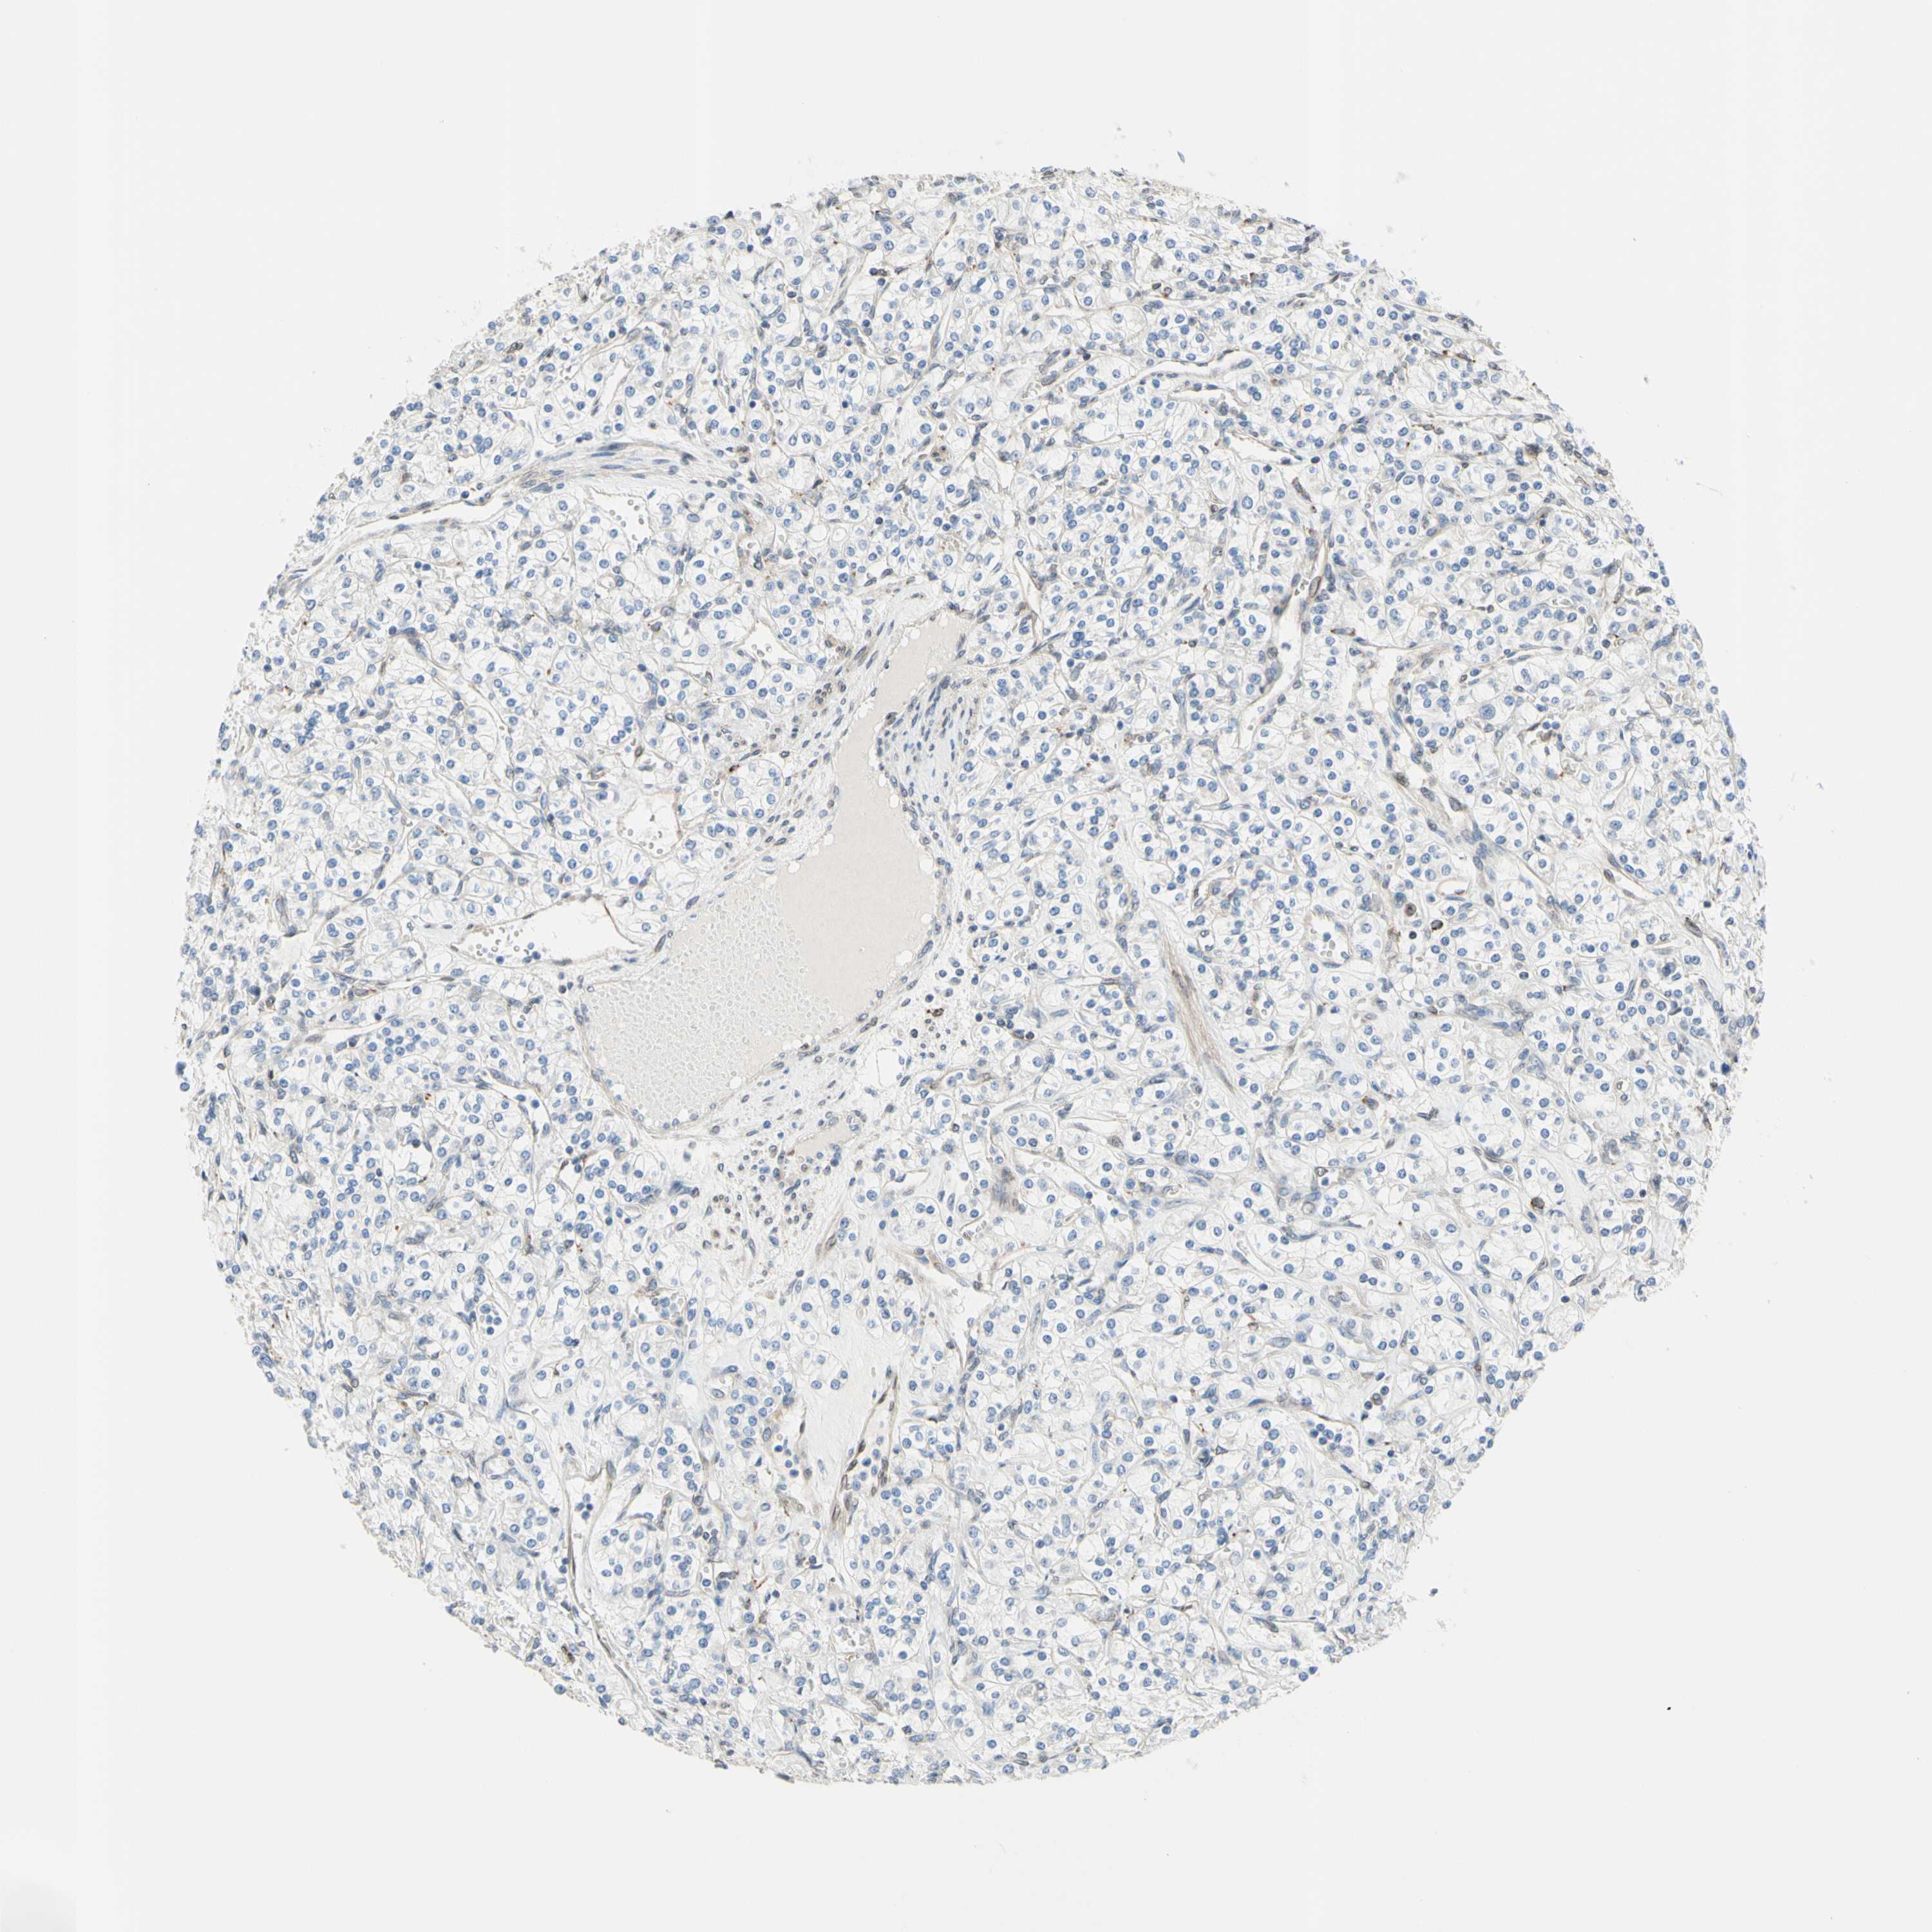

KIDNEY RENAL PAPILLARY CELL CARCINOMA (TCGA) - Interactive survival scatter ploti

The Survival Scatter plot shows the clinical status (i.e. dead or alive) for all individuals in the patient cohort, based on the same data that underlies the corresponding Kaplan-Meier plots. Patients that are alive at last time for follow-up are shown in blue and patients who have died during the study are shown in red.

The x-axis shows the expression levels (FPKM) of the investigated gene in the tumor tissue at the time of diagnosis. The y-axis shows the follow-up time after diagnosis (years). Both axes are complimented with kernel density curves demonstrating the data density over the axes. The top density plot shows the expression levels (FPKM) distribution among dead (red) and alive patients (blue). The right density plot shows the data density of the survived years of dead patients with high and low expression levels respectively, stratified using the cutoff indicated by the vertical dashed line through the Survival Scatter plot. This cutoff is automatically defined based on the FPKM cutoff that minimizes the p-score. The cutoff can be changed by dragging the vertical line or by entering a cutoff value in the square labeled "Current cut-off".

Under the Survival Scatter plot the p-score landscape (black curve; left axis) is shown together with dead median separation (red curve; right axis). Dead median separation is the difference in median mRNA expression between patients who have died with high and low expression, respectively. It is calculated as follows: median FPKM expression of dead patients with high expression - median FPKM expression of dead patients with low expression. This is intended to aid the user in visually exploring custom cutoffs and the associated p-scores and dead median separation.

Individual patient data is displayed and can be filtered by clicking on one or more of the category buttons on the top of the page. Categories describing expression level and patient information include: high, low, alive, dead, female, male and tumor stages. The scale of the x-axis can be toggled between linear and log-scale by clicking on the "x log" button. Mouse-over function shows TCGA ID, patient information and mRNA expression (FPKM) for each patient.

& Survival analysisi

Kaplan-Meier plots summarize results from analysis of correlation between mRNA expression level and patient survival. Patients were divided based on level of expression into one of the two groups "low" (under cut off) or "high" (over cut off). X-axis shows time for survival (years) and y-axis shows the probability of survival, where 1.0 corresponds to 100 percent.

TRAF2 is not prognostic in Kidney Renal Papillary Cell Carcinoma (TCGA)

Best expression cut offi

Based on the FPKM value of each gene, patients were classified into two groups and association between prognosis (survival) and gene expression (FPKM) was examined. The best expression cut-off refers the FPKM value that yields maximal difference with regard to survival between the two groups at the lowest log-rank P-value. Best expression cut-off was selected based on survival analysis .